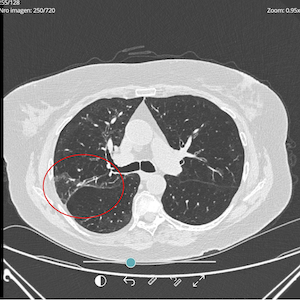

PRE-TREATMENT

OCTOBER 2024

POST-TREATMENT

SEPTEMBER 2025